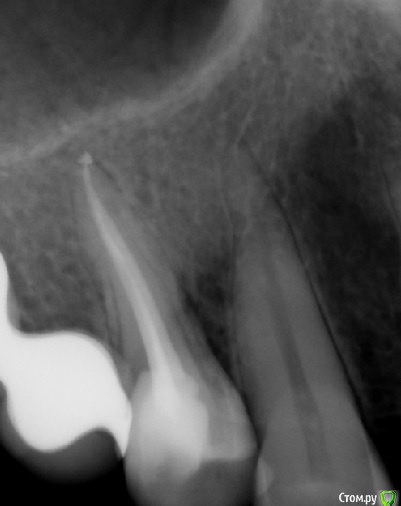

tatsiana.ma Опубликовано 12 мая, 2017 Поделиться Опубликовано 12 мая, 2017 (изменено) Добрый день!Имеются зубы 14 - 26 - (27, 28 удалены более полугода назад, это единственный депульпированный зуб на той стороне) Лечены около полутора года назад с разницей в пару месяцев: 14 - пульпит, в 26 - перидонтит. Сразу после лечения 14 зуб отзывался резкой болью при жевательной нагрузке и при прикосновении к нему, но врач настаивал, что это лишь постпломбировочные боли, но боль не проходила и не уменьшалась в течении нескольких месяцев, после чего врач просто занизил пломбу и фактически вывел зуб из прикуса. После таких манипуляций боль уменьшилась.По факту, оба этих зуба, если надавить пальцем на внешнюю стенку, тихонько и противно ноют, по минуты 3-4-5, потом вроде и спокойно. На прицельных снимках виден вывод пломбировочного материала за апекс. После пломбировки появилась небольшая припухлость щеки и справа и слева, в проекции верхушек корней этих зубов. Смущает, что из всех депульпированных зубов я чувствую только эти два 14 и 26, остальные зубы стоят себе спокойно. Также эти два зуба лечены с применением силера adseal, в других AHplus. Возможно ли, что такие ноющие боли и отечность как реакция раздражения на выведенный за апекс материал и/или проявление аллергической реакции? Имеет ли смысл перепломбировать эти зубы с применением AHplus? p/s/ Сдавала кровь на общий igE - в норме, аллергию непосредственно на пломбировочные материалы у нас не делают. Изменено 12 мая, 2017 пользователем tatsiana.ma Ссылка на комментарий

tatsiana.ma Опубликовано 12 мая, 2017 Автор Поделиться Опубликовано 12 мая, 2017 Желательно сделать томограмму и поискать непройденные каналы КТ перед лечением делала, все каналы найдены:в 14 два канала - первичное эндо,в 26 четыре канала - рэндо, периодонтит (был пропущен 4-й), на контрольном кт гранулёма ушла.Но вот эти странные ощущения и ноющие боли при нажатии... с момента лечения и на протяжении полутора лет сохраняются. С февраля по май этого года выполнено рэндо других четырёх зубов - все ок, никаких посторонних ощущений (делал другой врач). Ссылка на комментарий